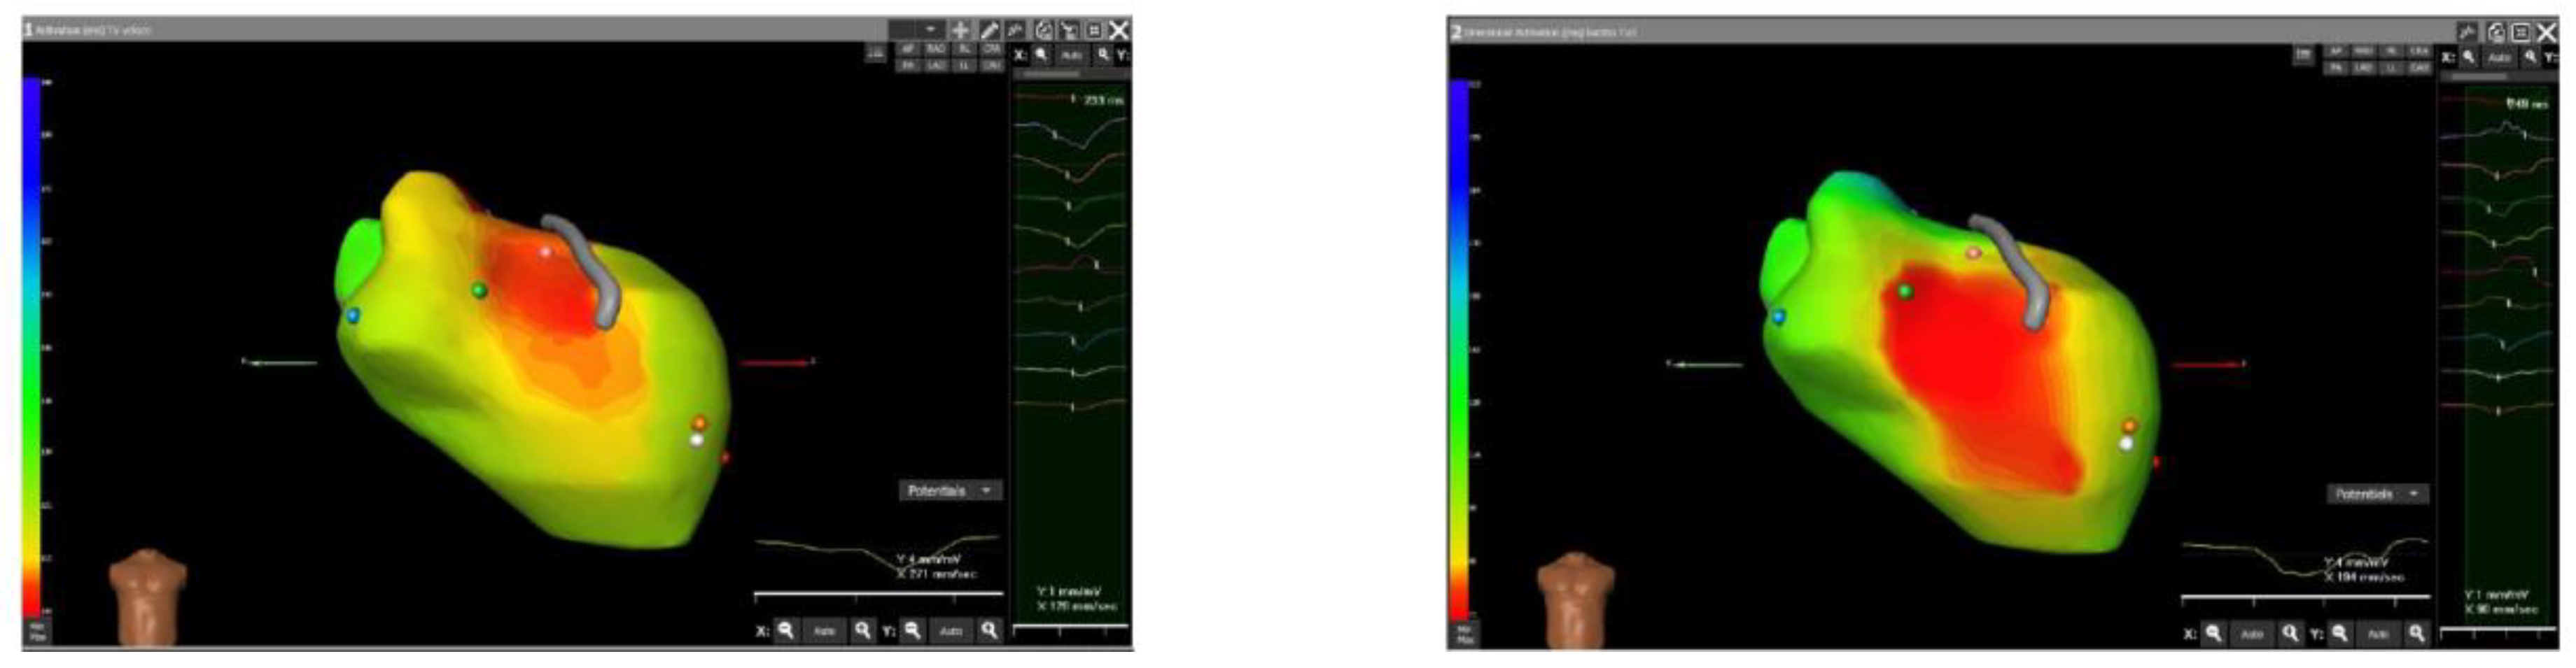

2. Case Presentation